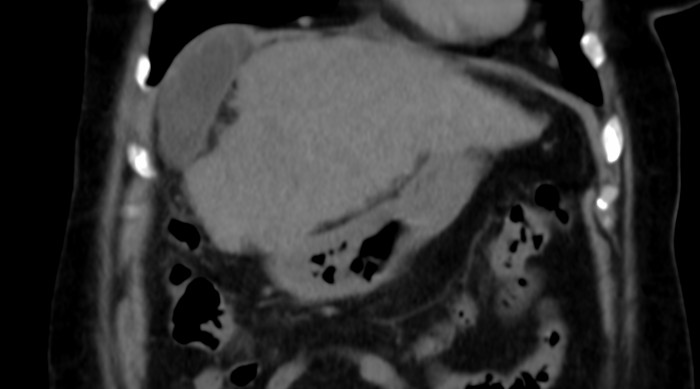

Presentamos el caso de un paciente con diagnóstico de cáncer de mama derecha triple negativo, para el cual se solicita estudio de extensión para estadificación. Se realizó tomografía (TC) de tórax y abdomen simple identificando la vesícula biliar de situación suprahepática (Figs. 1 y 2) asociado a hipoplasia del lóbulo derecho (Fig. 3), así como escaso líquido perivesicular (Fig. 4); no hay lesiones hepáticas que sugieran actividad metastásica. En el resto del estudio no se identificaron alteraciones, ni variantes anatómicas.

Figura 3

TC de abdomen corte sagital. Se observa la hipoplasia hepática del lóbulo derecho.